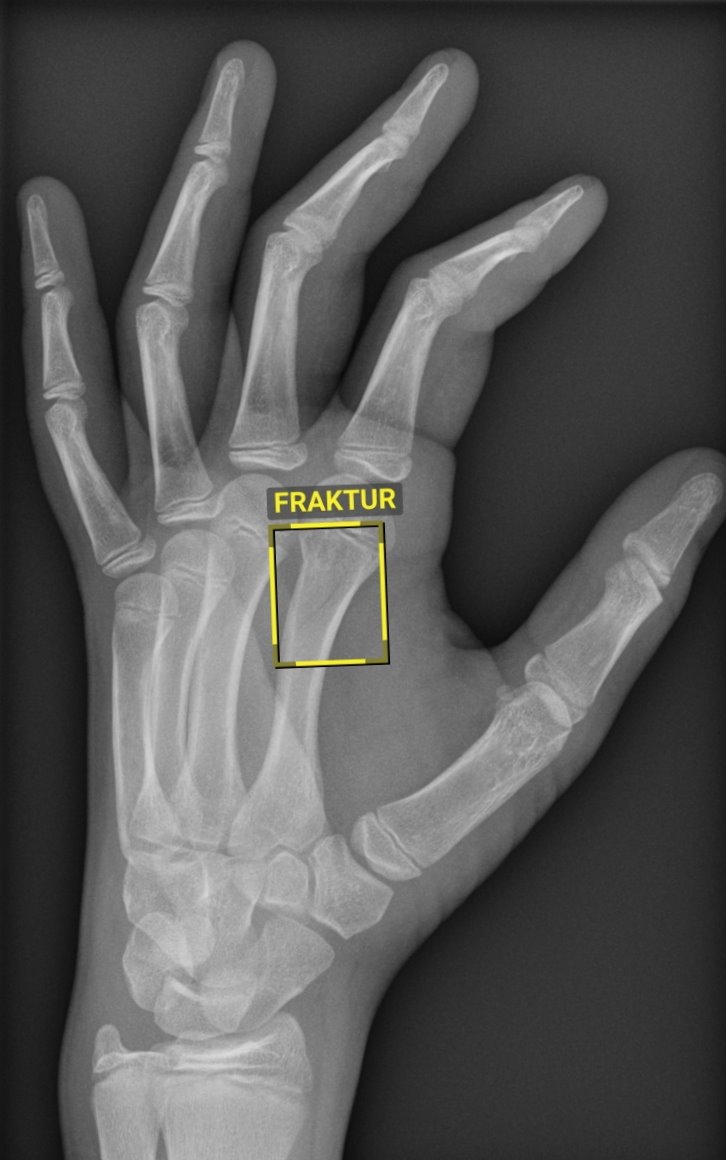

Das System erkennt selbst feinste oder überlagerte Knochenbrüche und kennzeichnet sie mit einem Rahmen. Gerade einmal 90 Sekunden benötigt es dafür. Zur weiteren Analyse und finalen Diagnose wird den Medizinern im Anschluss das vollständige Röntgenbild mit den Markierungen der KI auf den Bildschirm gespielt. „Die Künstliche Intelligenz kann den Radiologen dabei niemals ersetzen und arbeitet auch nicht besser als der Mensch. Sie ist wie ein zweites Paar Augen, das den Ärzten assistiert, oder wie ein Kopilot, der zur Unterstützung mit im Cockpit sitzt. Die Verantwortung für eine korrekte Diagnose obliegt dabei weiterhin den Ärzten“, sagt Prof. Dr. Ali Seif, Direktor des Instituts für Klinische und Interventionelle Radiologie.

Anwendung findet die neue Technik zunächst in der Unfallchirurgie zur Diagnostik von Knochenfrakturen. Weitere Schritte sind an der UMG allerdings bereits in Vorbereitung: So steht die Systemeinführung für Röntgenaufnahmen der Lunge bereits unmittelbar bevor. Später soll die KI auch in der Bildgebung für den gesamten Thorax, also den Brustkorbbereich, eingesetzt werden.